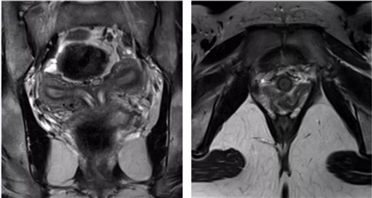

双子宫

双侧副中肾管未融合,各自发育成两个子宫、宫颈和阴道。75%伴阴道纵隔或斜隔

两个独立的子宫、宫颈、阴道,T2WI解剖分层正常